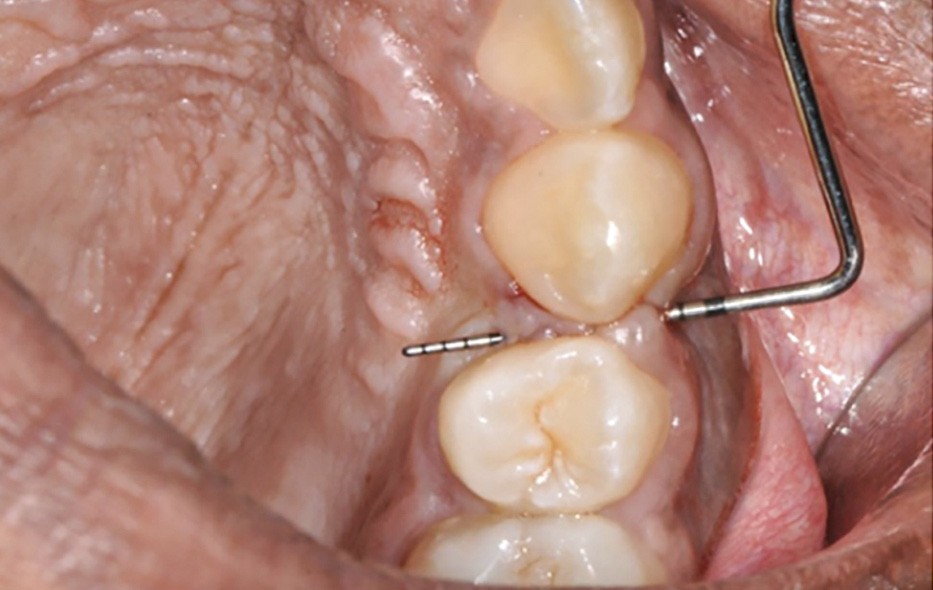

Des avulsions sont réalisées dans 15 % des traitements d’orthodontie [1], principalement en cas d’encombrement sévère ou de vestibuloversion incisive marquée. Les fentes gingivales sont des défauts parodontaux fréquemment observés lors de la fermeture orthodontique d’un espace d’avulsion (dans 35 à 100 % des cas selon les auteurs [2-7]) (fig. 1).

La fente est définie comme une invagination linéaire du tissu interdentaire en direction mésiale ou distale avec une profondeur de sondage d’au moins 1 [2] ou 2 mm [3]. Elle se présente sous forme d’un pli (ou fissure) de gencive plus ou moins sévère pouvant cacher un défaut osseux sous-jacent.